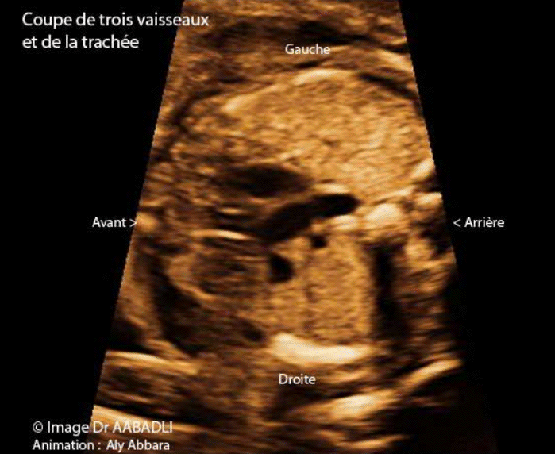

مقطع الثلاث أوعية والرُغامى أو مقطع ياكيل الشاوي

(La coupe de trois vaisseaux et la trachée)

أنه مقطعٌ علويٌ وعرضيٌ للمنصف ـ الشريان الأبهري يشكل مع الشريان الرئوي زاوية حادة مع نقطة تقاطعٍ متجهة نحو الخلف وإلى يسار العمود الفقري

المقطع العرضي للرغامى يمر في نهايتها السفلية، ولذلك عندما ننزل قليلاً بالمسبار الصدوي نحو الأسفل يمكننا أن نلاحظ ظهور مقطعٍ عرضيٍ للقصبة اليمنى واليسرى بدل المقطع الرغامي

Il s'agit d'une coupe transversale du médiastin au niveau de la crosse de l'aorte ; sur cette coupe l'aorte et l'artère pulmonaire dessinent un lettre "V" dont le somment est dirigé vers l'arrière et à gauche de la colonne vertébrale.

La coupe de la trachée passe au niveau de son extrémité distale, juste avant sa division en deux bronches, donc en dirigeant légèrement la sonde échographique vers le bas, on peut voir la coupe transversale de la trachée remplacée par deux coupes transversales, il s'agit des bronches droite et gauche.

هذا المقطع مهمٌ جداُ في تشخيص العديد من تشوهات القلب عند الجنين حيث ينقص من المقطع أحياناً واحدٌ من العناصر التشريحية المكونة له كما هو الحال في ـ اِنقلاب وضع الأوعية الكبيرة ـ عندئذ نرى على المقطع شريانٌ طوليٌ واحدٌ فقط و بجانبه مقطعُ الوريد الأجوف العلوي والرغامى

Cette coupe est très utile pour la mise en évidence de certaines anomalies congénitales cardiaques, en particulier, la transposition de gros vaisseaux, où on peut observer la présence d'un seul vaisseau artériel avec la veine cave supérieure et la trachée en juxtaposition avec cette artère.